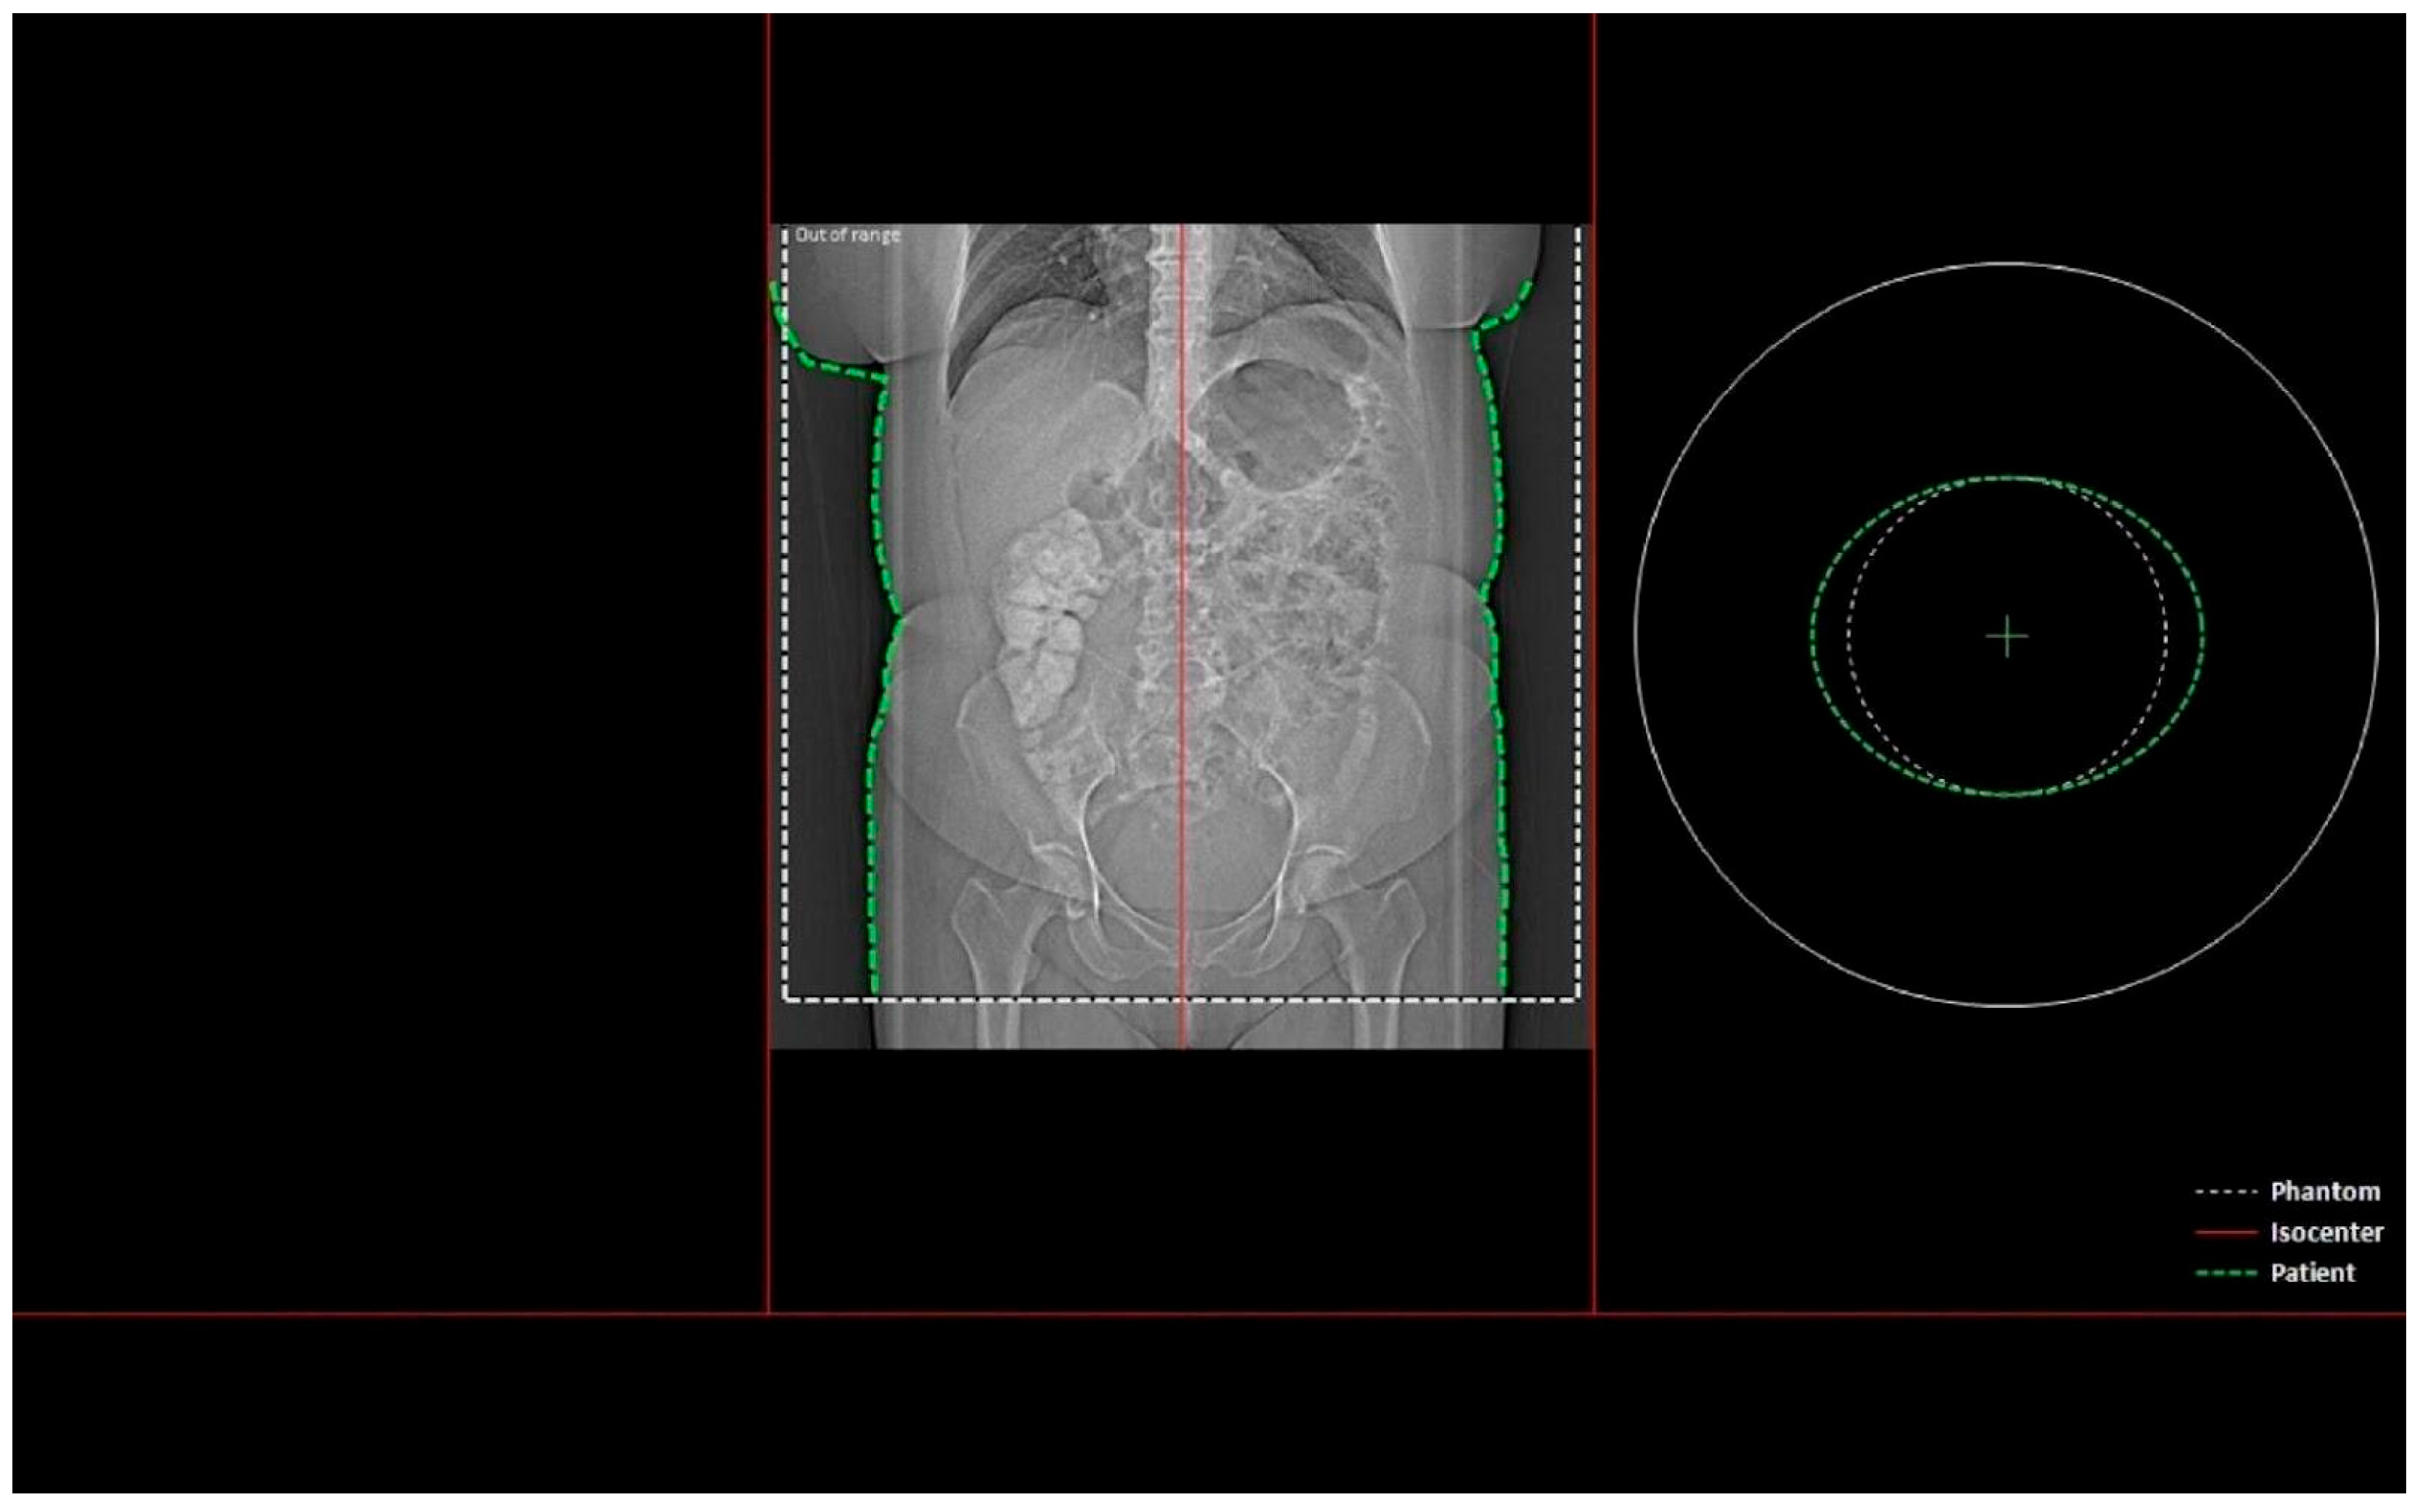

- Whether the patient was in the isocenter—Figure 1 shows the patient outside the isocenter, while Figure 2 shows the patient inside the isocenter.

Figure 1. Image from the Dose&Care system showing patient placement outside the isocenter.